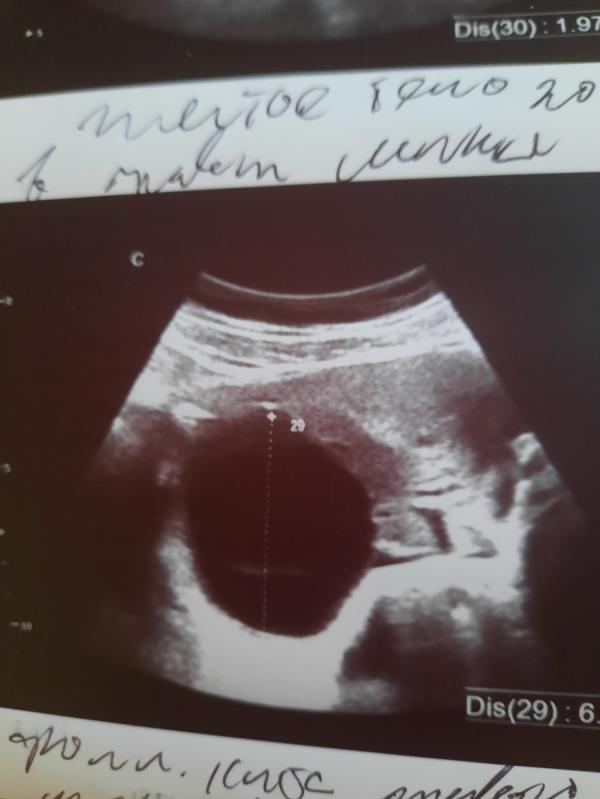

У меня 3 недели беременности, я была на узи,протекает беременность хорошо. Но еще обнаружили кисту 6 с половиной см. Очень переживаю.. Может кто-то что-то подскажет?

Кисту чего? Яичник, матка? В беременность кисты частое явление. Я о своей кисье яичника узнала как раз в беременность. Она росла и очень быстро. В 5 недель была 27мм, к 11 неделям она стала 57 мм. Сильные боли были из-за неё. Потом резко все прошло и киста прошла